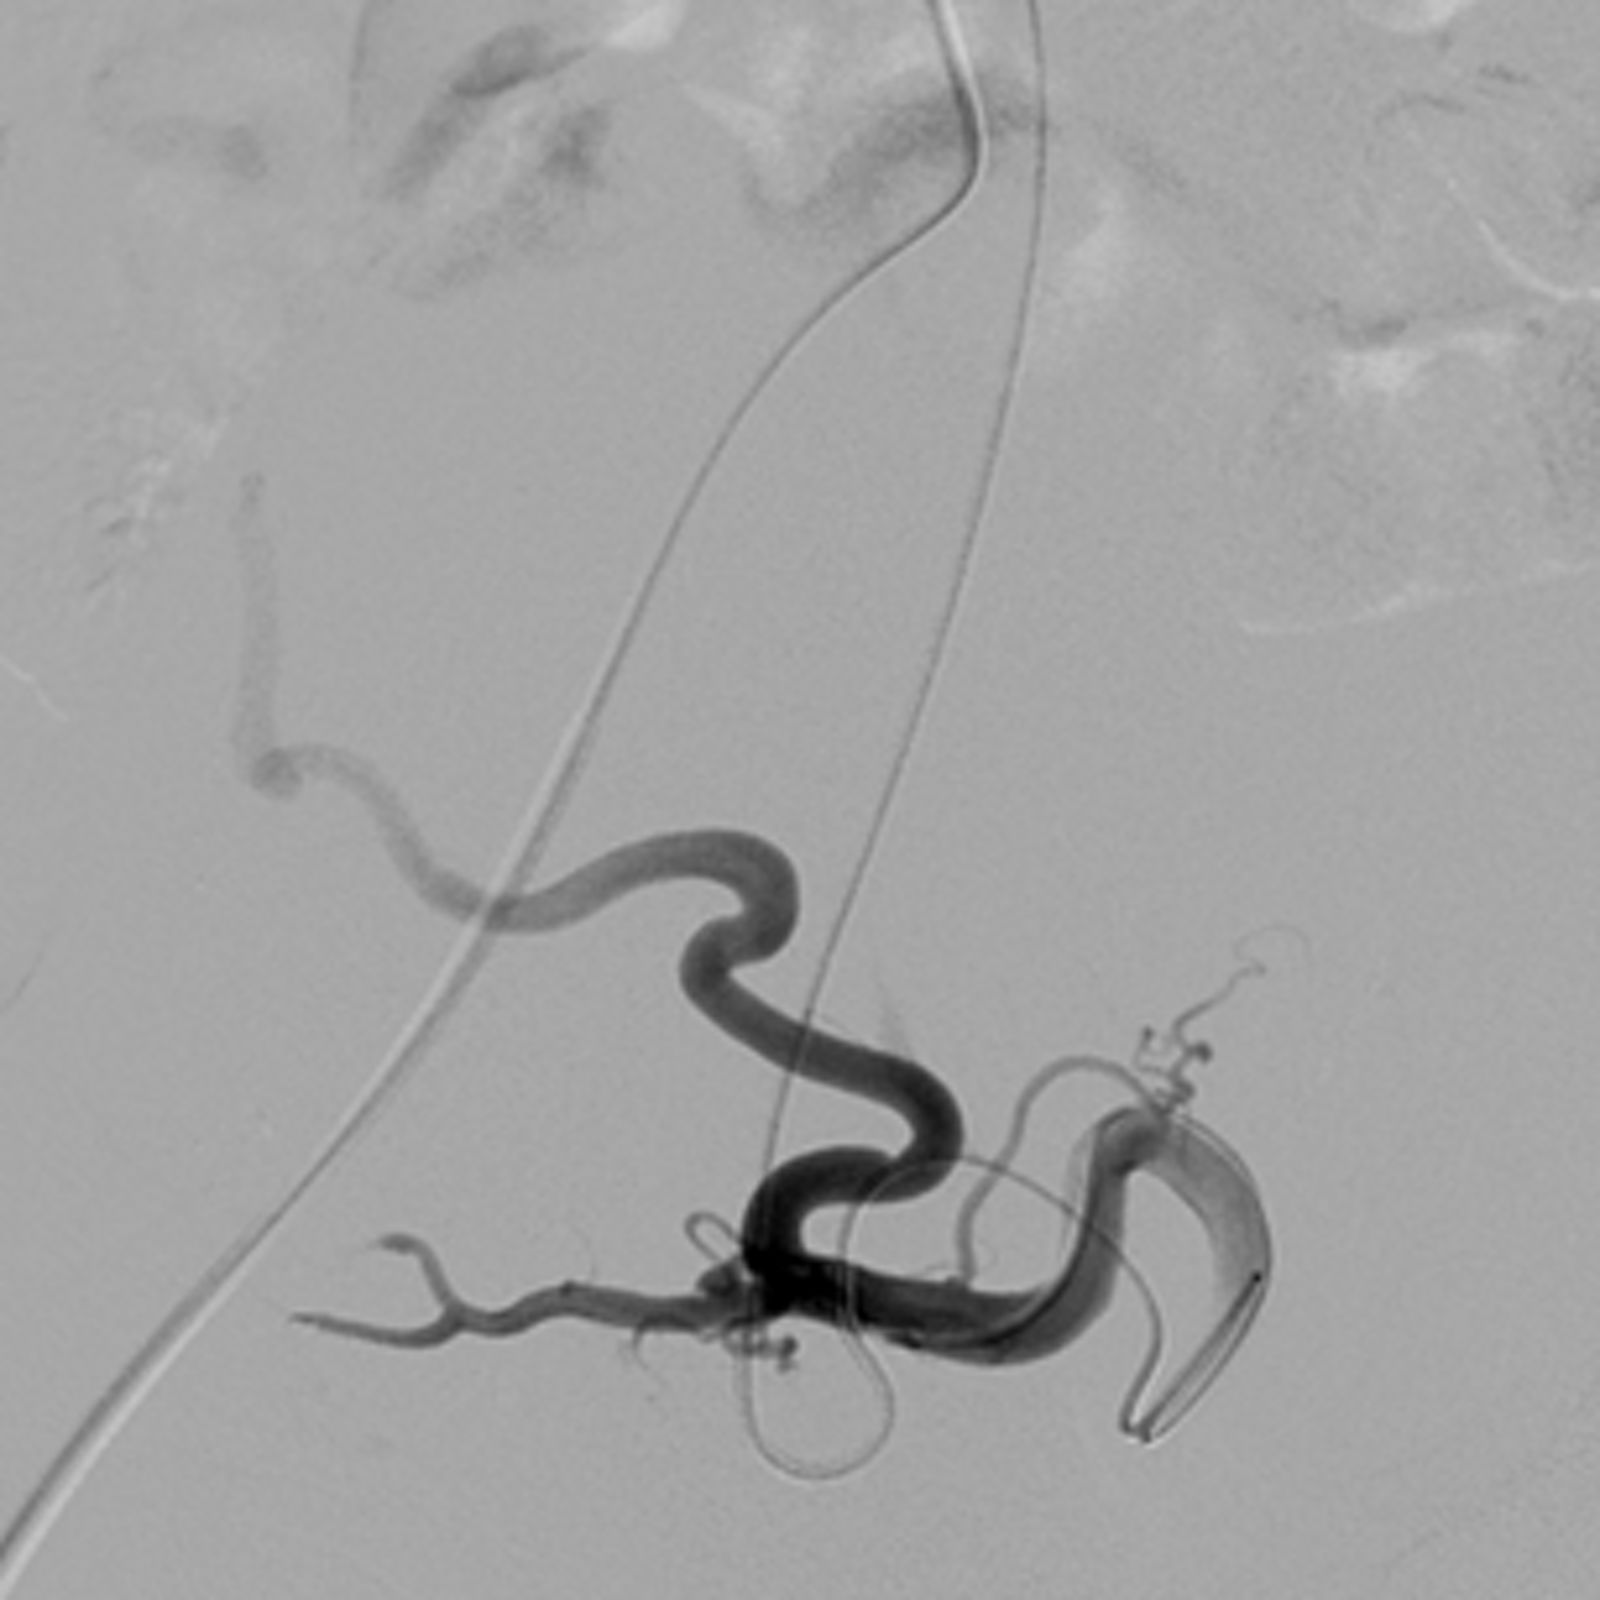

Der Eingriff erfordert nur einen kleinen Einschnitt in der Leistengegend. Unter Röntgenkontrolle führen wir einen Katheter mit einem Durchmesser von weniger als einem Millimeter durch die Blutgefäße zu der Arterie vor, die das Myom mit Blut versorgt. Anschließend wird das Blutgefäß mit winzig kleinen Kunststoffkügelchen verschlossen (embolisiert).

Vergleich der Myom-Durchblutung vor und nach der Embolisation